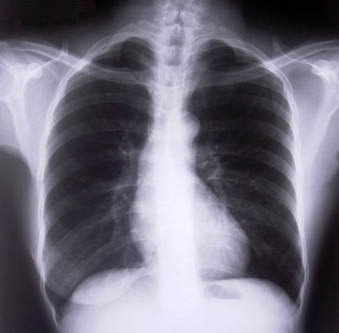

The prevalence of tuberculosis (TB) is on the rise and Pakistan now ranks fourth in terms of the highest number of cases in the world, moving up four places from its previous position.

“It is estimated that over 400,000 new cases of TB are reported in Pakistan every year,” he stated. He expressed concern over the rapid spread of respiratory diseases, including TB, ailments caused by pollution, tobacco dependence and active and passive hazards of smoking, allergies and asthma.

Prof. Kamran Chima, the newly-elected president of Pakistan Chest Society, said the prevalence of TB has risen to 276 cases per 100,000, and suggested an aggressive campaign against multi-drug resistant TB.